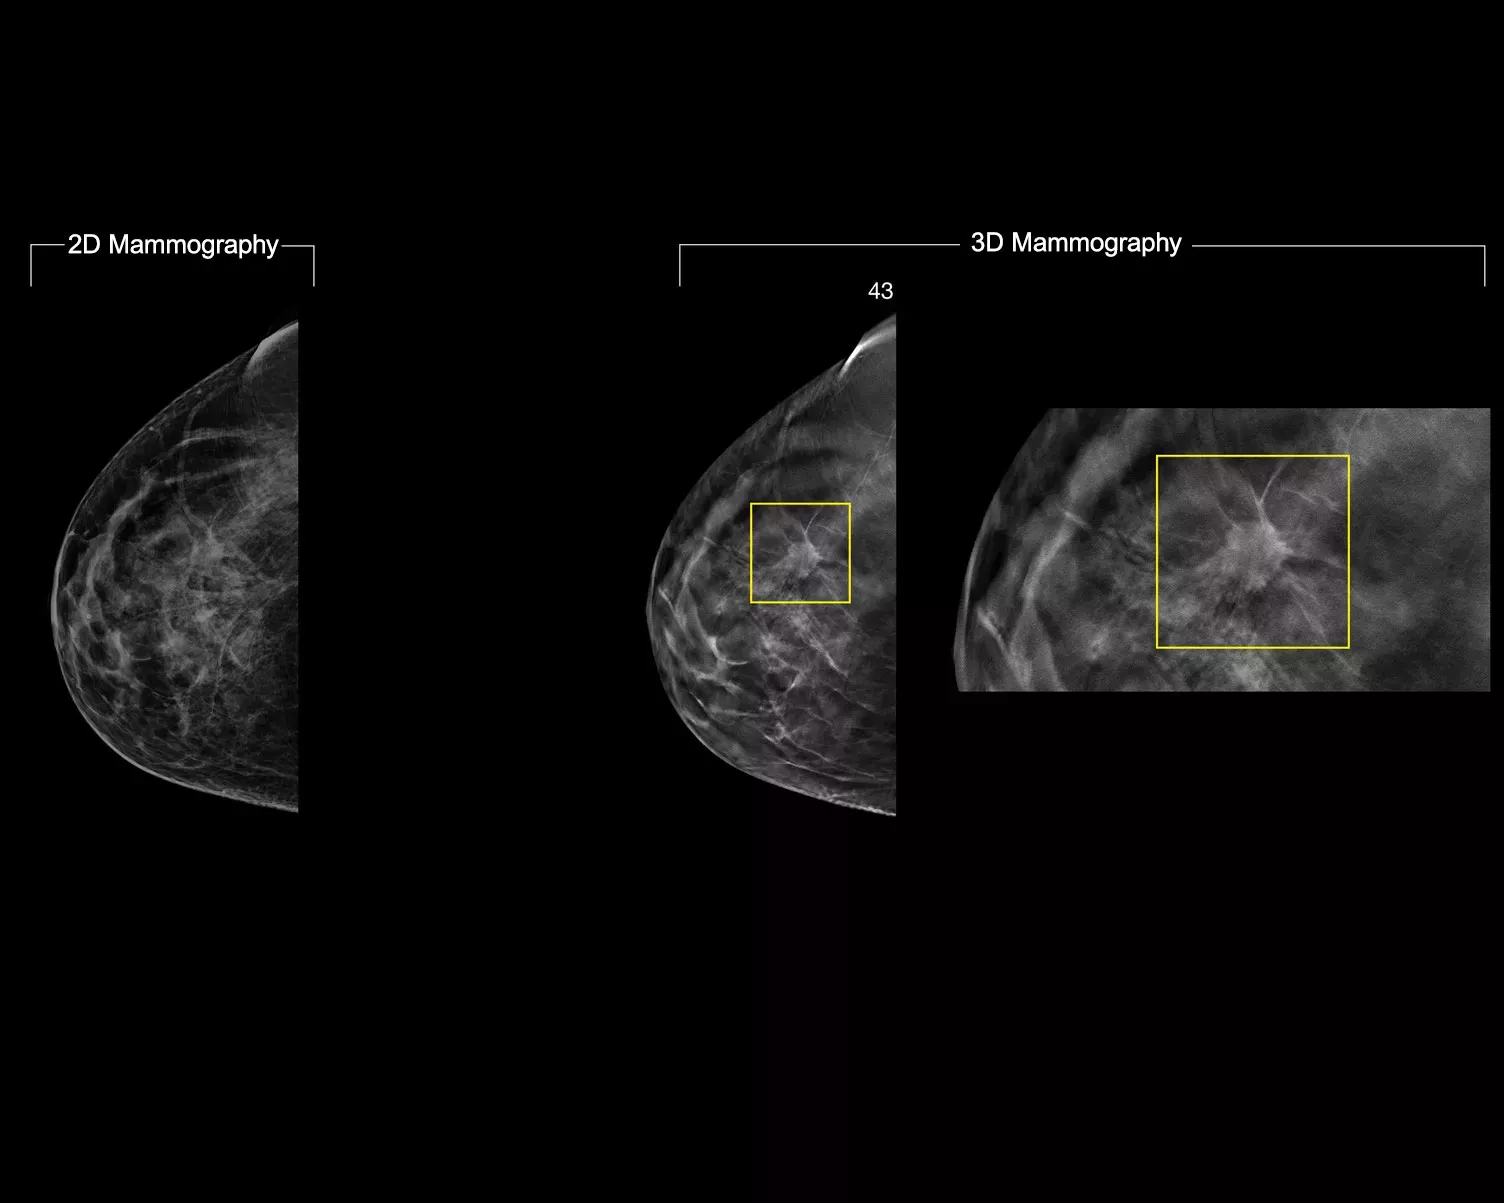

In a constantly changing clinical mammography environment, the flexibility and compatibility of ImageChecker 2D CAD Technology provides detection for conventional 2D images, as well as C-View™ and Intelligent 2D™ synthesised images derived from a tomosynthesis dataset.

- Easy navigation to the slice of interest in the tomosynthesis stack, when used in combination with Smart Mapping on synthesized 2D images

Image Gallery3